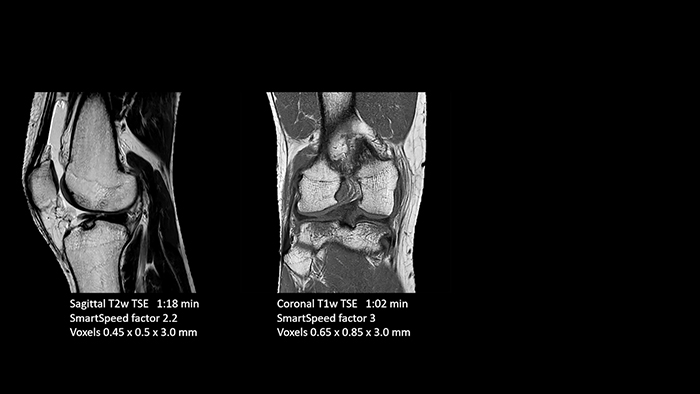

SmartSpeed is used to reduce scan times. All three PDw orientations were obtained with only one 3D sequence using SmartSpeed. Performed with 1.5T Ambition X, 16ch dS Knee coil.